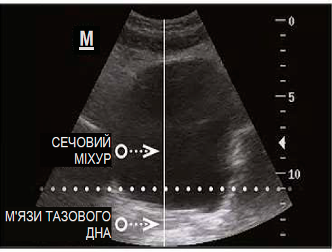

ДО

Вихідні порушення:

ПІСЛЯ

Механізм лікувальної дії: